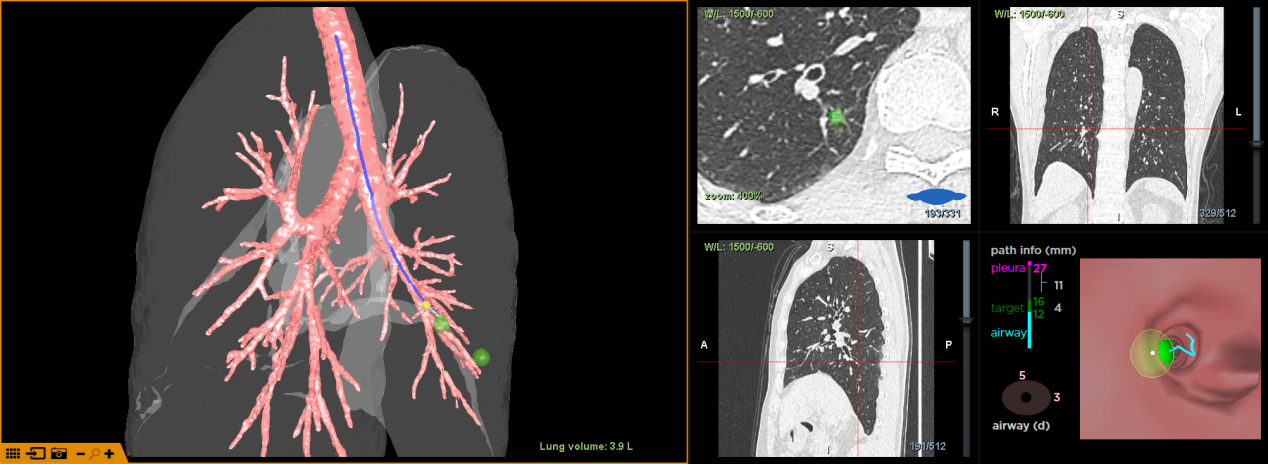

术前,通过导航系统对患者进行CT三维重建规划,评估分析,患者病灶位于右肺下叶后基底段,大小约10mm*9mm,距离胸膜有一定距离。为精准定位肺结节,明确切除范围,同时尽可能保留正常肺组织,金龙玉教授团队决定应用增强现实光学导航系统引导下,在气道内使用一次性使用肺外科H-Marker金属标记物定位肺结节,行胸腔镜下微创肺结节切除术。

图二:术前评估H-Marker放置点与病灶相对位置

术中进镜顺利,增强现实光学导航系统实时匹配引导至右肺下叶后基底段,随后在规划好的位置释放H-Marker。释放后,手术团队依据标记物指引快速定位结节,遂行胸腔镜下肺楔形切除术,术后切除的标本可以清晰看到灰白色癌性结节已被精准切除,H-Marker位于结节边缘,定位精准。最终病理结果示:(右下肺结节)贴壁生长方式为主的腺癌,考虑贴壁型腺癌(LPA)。